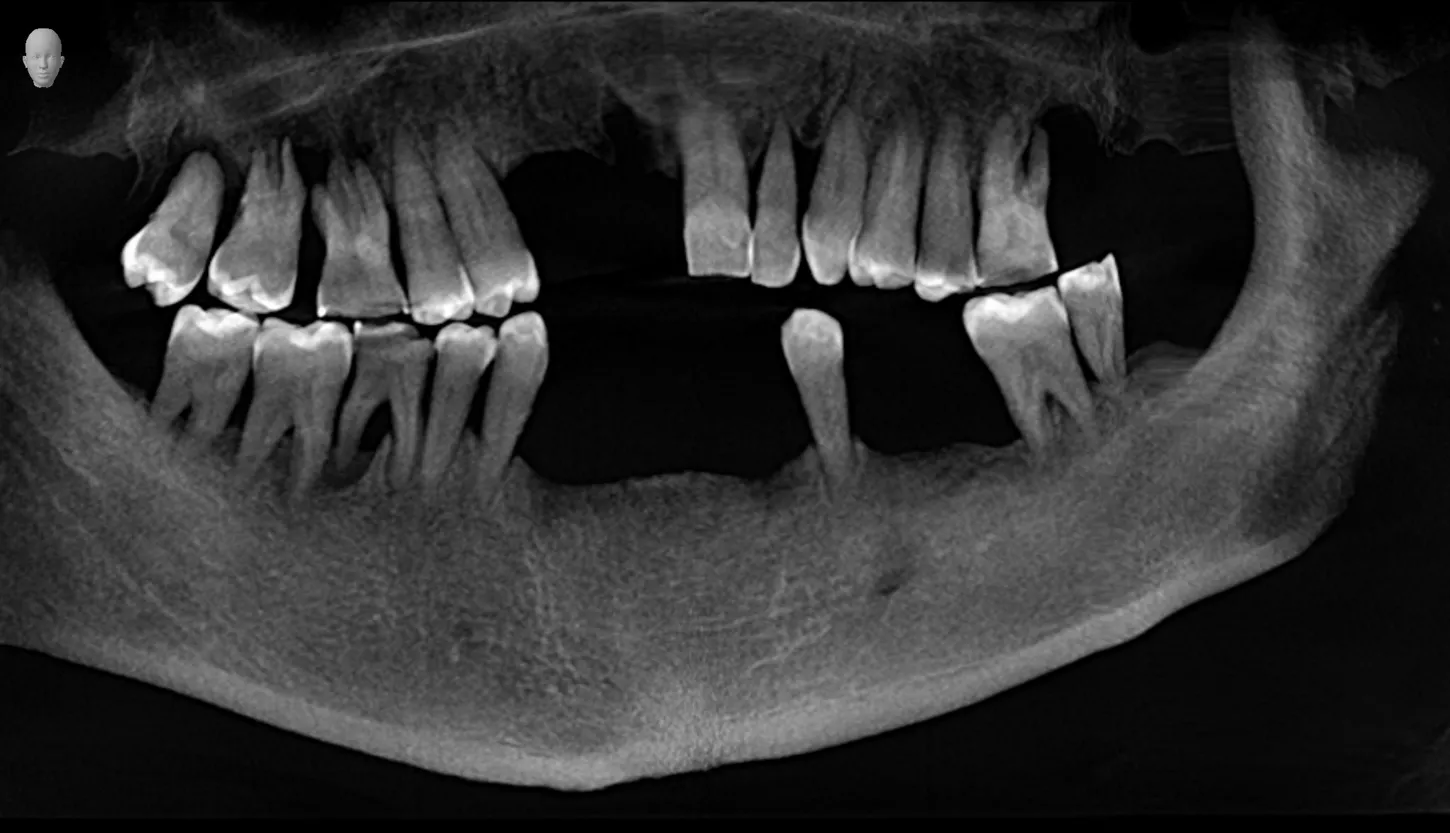

1. Panoramic radiograph view before extraction of teeth in the mandible and maxilla.

1